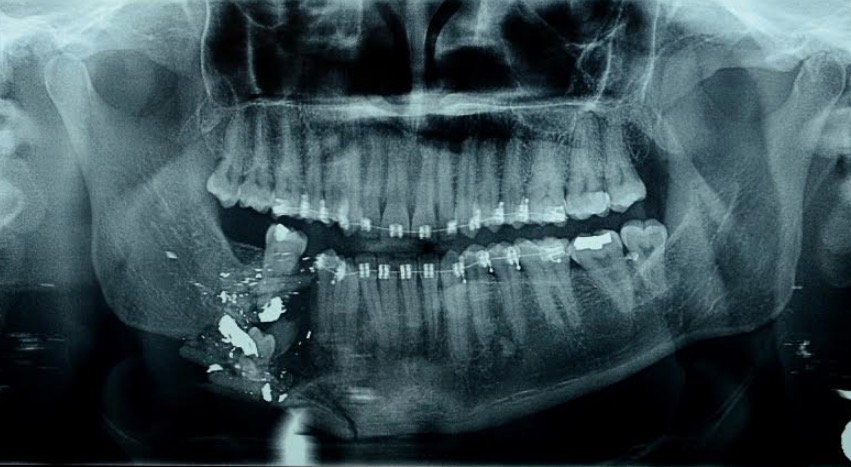

Inédita, a cirurgia consistiu em transplantar retalho microcirúrgico da fíbula do paciente – osso da perna, antigo perônio, ao lado da tíbia (canela), pela parte externa. O paciente, servidor público da área de segurança pública, foi vítima de ferimento na face por arma de fogo, afetando diretamente a mandíbula direita, no dia 22 de abril.

O cirurgião bucomaxilofacial Francisco Amadis destacou que a cirurgia reconstruiu parte do osso da mandíbula. “Boa parte da mandíbula direita foi destruída pelo projétil. Trabalhamos em parceria com cirurgião plástico, especialista em microcirurgia. Enquanto uma equipe preparou o local para receber o retalho microvascular na mandíbula, a segunda equipe retirou o retalho da fíbula, da perna do paciente, para a reconstrução”, explicou Amadis.

Segundo o médico, a cirurgia foi realizada no momento ideal e o paciente irá recuperar a qualidade de vida. “Após mais de 30 dias do acidente, com todos os exames e procedimentos pré-operatórios realizados, reconstruímos a mandíbula, devolvendo qualidade de vida ao paciente”, disse Amadis.

“Com esta cirurgia, iremos devolver ao paciente a função mastigativa e de fonação, e articulação dos sons. Além de também devolver a deglutição”, informou Amadis. “O mais importante é o retorno do paciente ao convívio social e às suas atividades laborais”, complementou o médico.